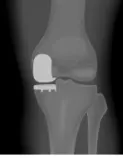

Q22: A 55-year-old male was diagnosed with right knee osteoarthritis. He was asking about partial (Unicompartmental) knee arthroplasty. What is the absolute contraindication for this procedure?

- D. Rheumatoid Arthritis

Q67: A 70-year-old male came with a history of knee pain, and his x-ray in the picture. What is appropriate treatment for him?

- A. Total knee replacement